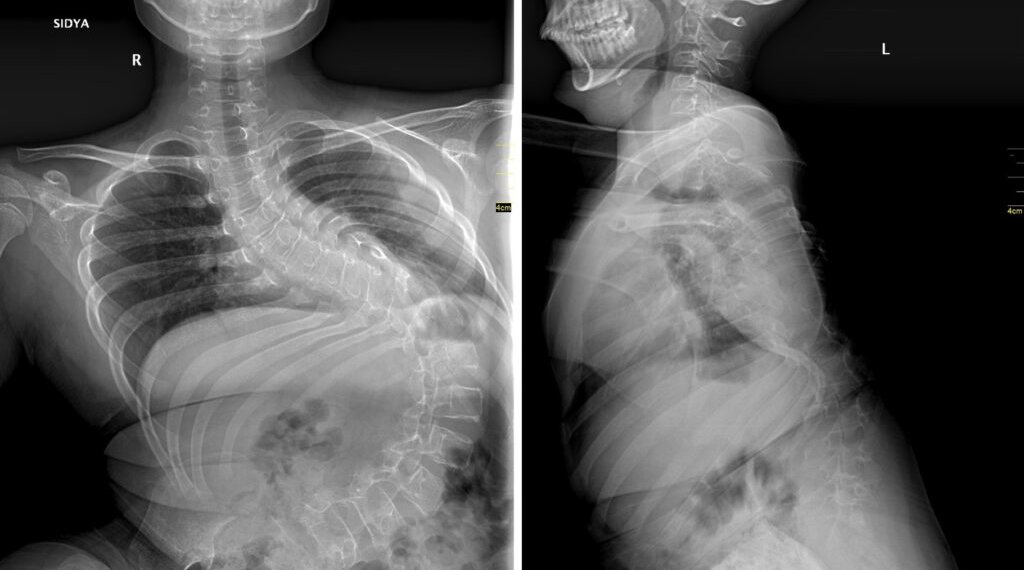

«Первым этапом хирургического лечения стала коррекция деформации позвоночника, поскольку она достигала уже критических значений — более 140 градусов искривления. Без своевременно выполненной операции сколиоз прогрессировал бы дальше, и мальчик не смог бы даже сидеть», — комментирует хирург-вертебролог Александр Васюра.

Деформацию удалось скорректировать до 32 градусов при исходных 143 градусах.